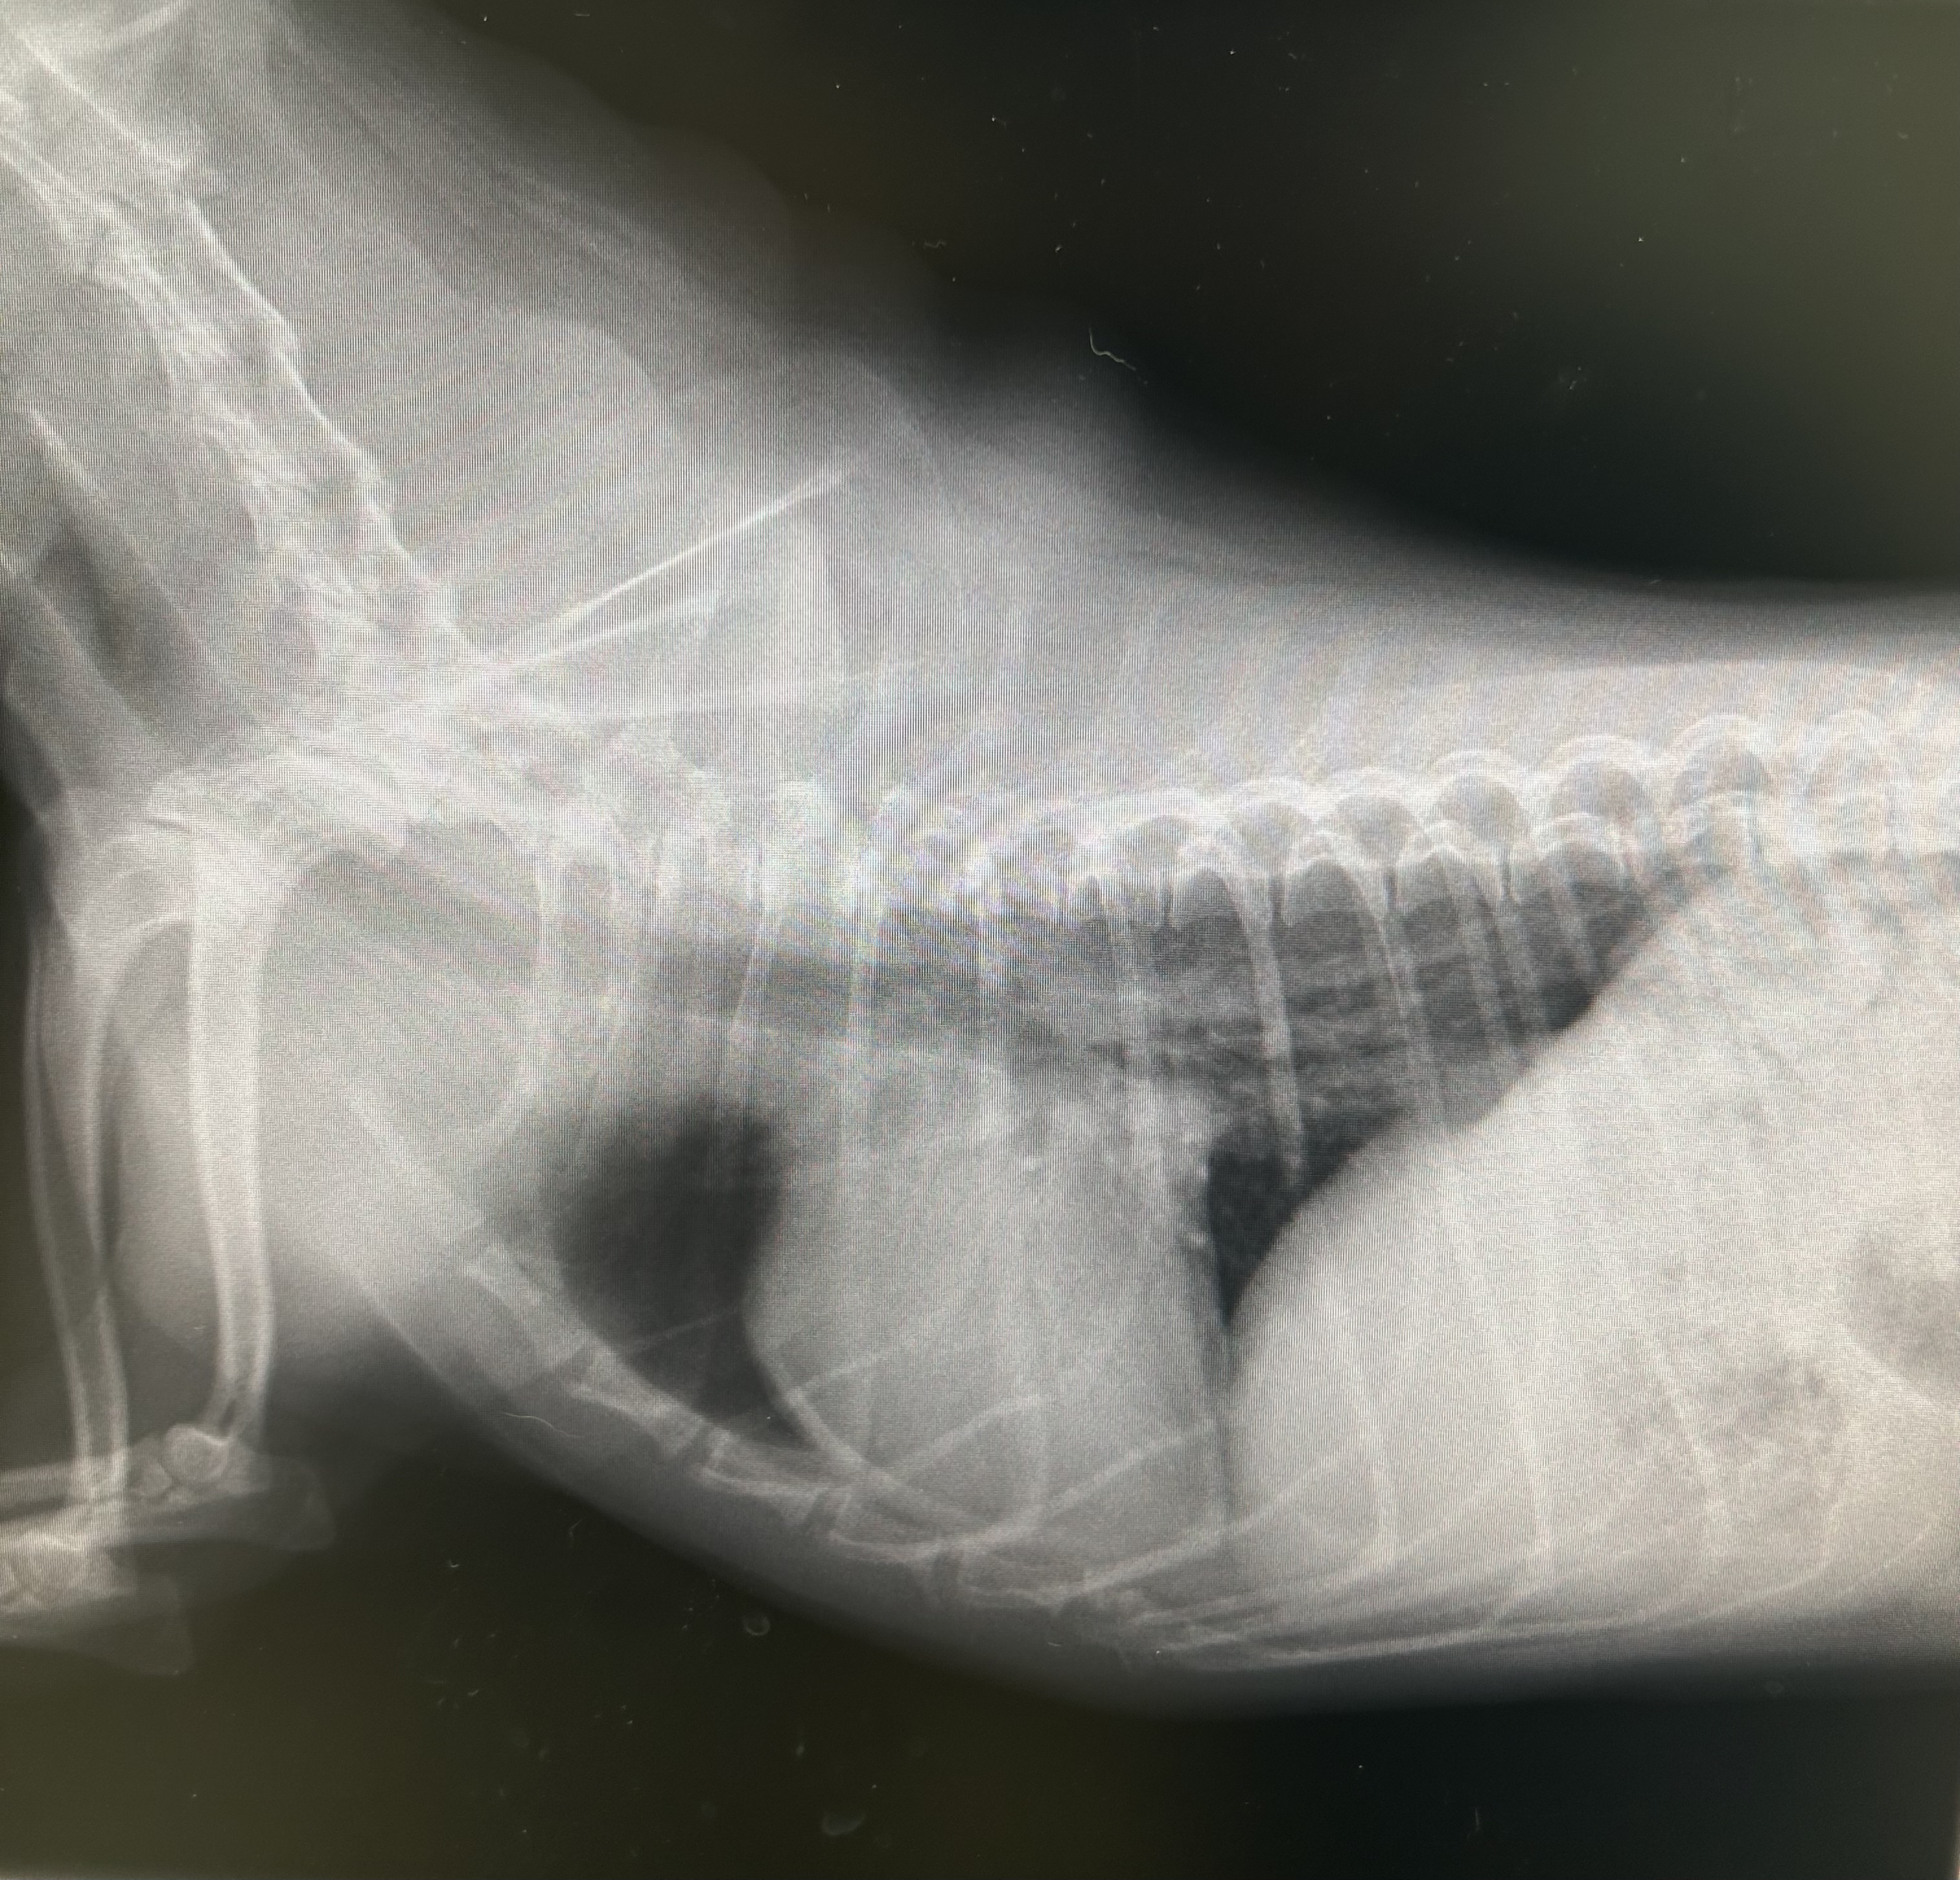

3. X線検査: 心臓に負担がかかって、心拡大が起きていないか調べられます。また、『肺水腫』が起きているかどうかもわかります。

治療後の写真